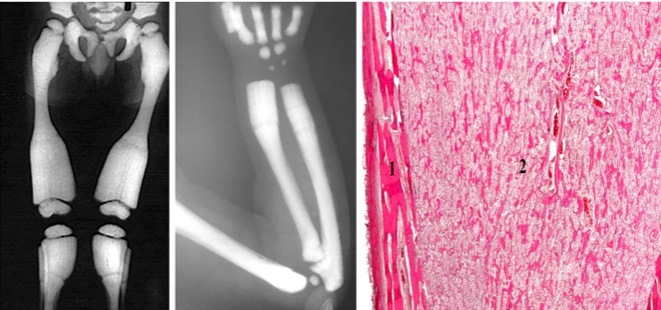

Vitamin D Deficiency: Osteomalacia & Rickets

Sx Children: bowed legs, pigeon breast, frontal bossing, rachitic rosary

Sx Adults: weak bone, easily fractured

Osteogenesis Imperfecta

X-ray: every bone has fractures (hyperdense areas showing callous formations)